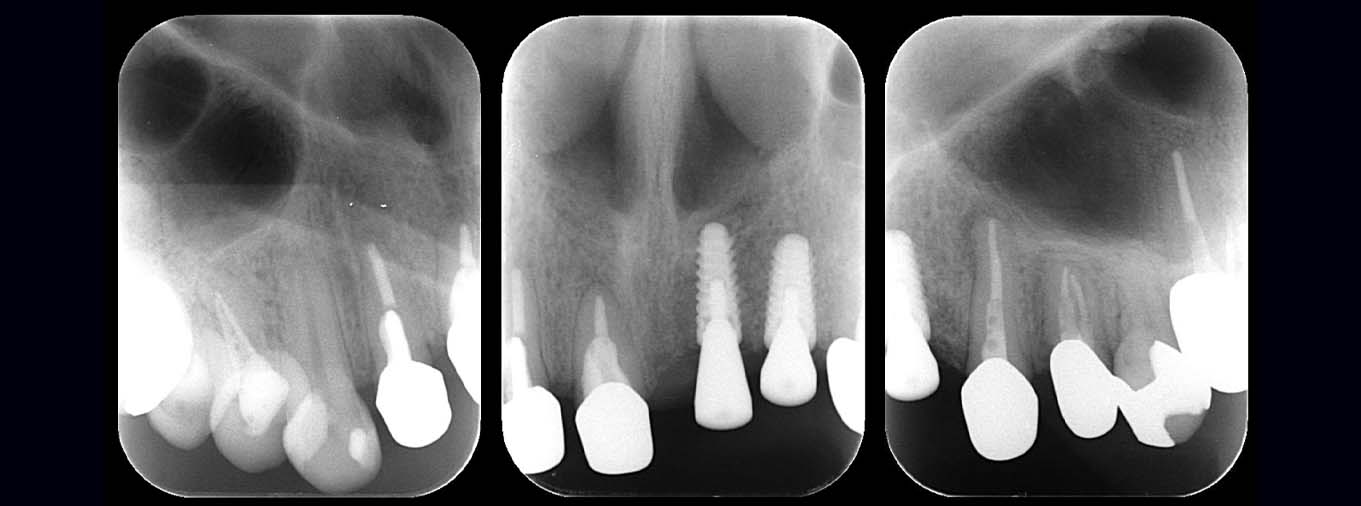

2.初診時エックス線写真

左上の1番奥の歯はすでに神経がとってあり、

大きなむし歯を認め根分岐部の歯周ポケットは8mmでした。

今回の症例では、歯根の途中にパーフォレーション(穴があいている)が認められ(黄矢印)、根の間の骨(青丸)が溶けていました(根分岐部病変)。